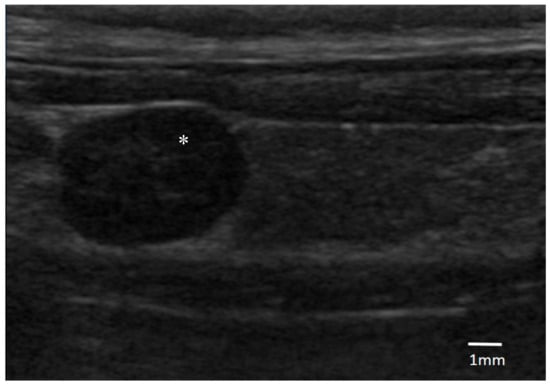

Regarding the cervical US findings, a parathyroid single nodule was identified in all of the dogs (median length 5.3 mm; range 3.5 to 6.5 mm). Five of them were on the right-side, and three on the left. Six nodules were cranially displaced and one was caudal. All of the masses had a similar ultrasonographic aspect being oval, well defined, and hypoechoic in comparison with the surrounding tissues (Figure 1).

Figure 1. Ultrasonographic image of an oval hypoechogenic parathyroid nodule of 6.5 mm diameter (*), surrounded by thyroid tissue (original, credits to Centre Hospitalier Vétérinaire (CHV) Fregis).

A parathyroid isolated hypoechoic nodule was identified in all of the dogs, reinforcing the diagnosis of PHPTH. Although a correlation between the ultrasound and surgical findings can be incongruent in several cases [19], these findings reinforced the value of cervical US in the diagnosis of PHPTH, allowing for a reasonable planning of percutaneous UG-RHA.